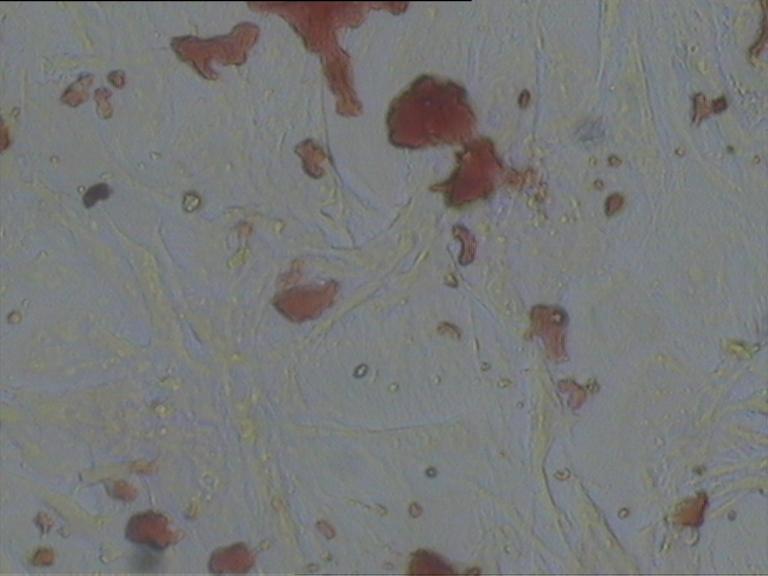

茜素紅染色【細胞染色】

對照組

給藥組

模型組